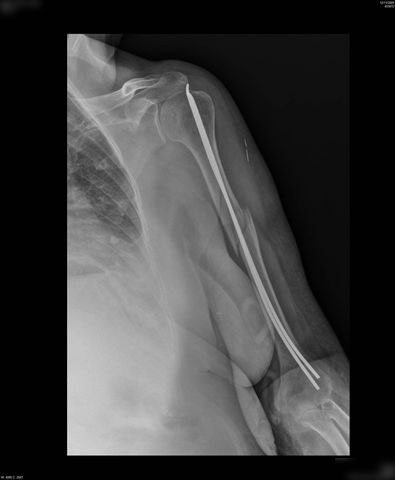

Fractura de diáfisis de húmero.

Fractura de húmero tras osteosíntesis con clavo gamma.